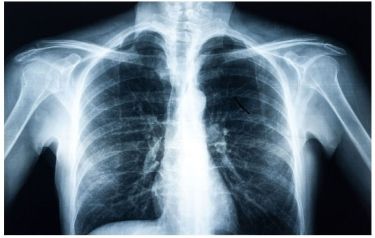

A new artificial intelligence model finds that X-ray images collected during routine medical care can provide warning signs for diabetes, even in patients who don’t meet the guidelines for elevated risk.

Each year, millions of Americans receive chest X-rays for chest pain, difficulty breathing, injury or before surgeries. Emory alone completes on average about 200,000 radiographs annually.

While radiologists are not looking for diabetes when they assess these X-rays, the images become part of a patient’s medical record and could be analysed later for diabetes or other conditions.

“Chest x-rays provide an ‘opportunistic’ alternative to universal diabetes testing,” says Judy Wawira Gichoya, MD, Assistant Professor of Radiology and Imaging Sciences, and the lead researcher from Emory.

The AI model was trained on more than 270,000 X-ray images from 160,000 patients, with deep learning determining the image features that best predicted a later diagnosis of diabetes. Because chest X-rays are not a common way to detect diabetes, the researchers also used explainable AI techniques to determine how and why the model made its determinations.

The methods pointed to the location of fatty tissue as important for determining risk, a logic that aligns with recent medical findings that visceral fat in the upper body and abdomen is associated with type 2 diabetes, insulin resistance, hypertension and other conditions.

In some cases, the chest X-ray warned of high diabetes risk as early as three years before the patient eventually received a diagnosis. The model’s output also provides a numerical risk score that could potentially help clinicians customize the treatment approach for patients.